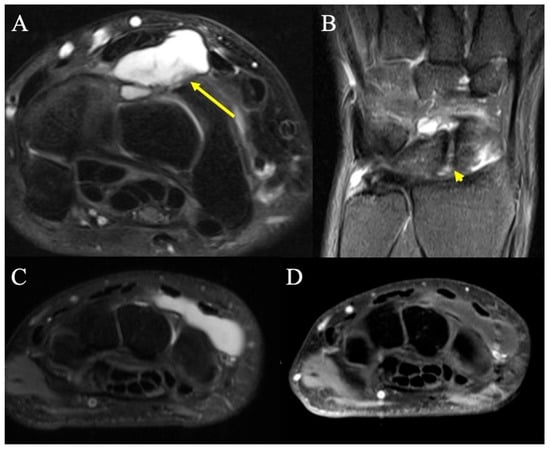

2.9. Infectious Tenosynovitis

2.9.2. Imaging Appearance